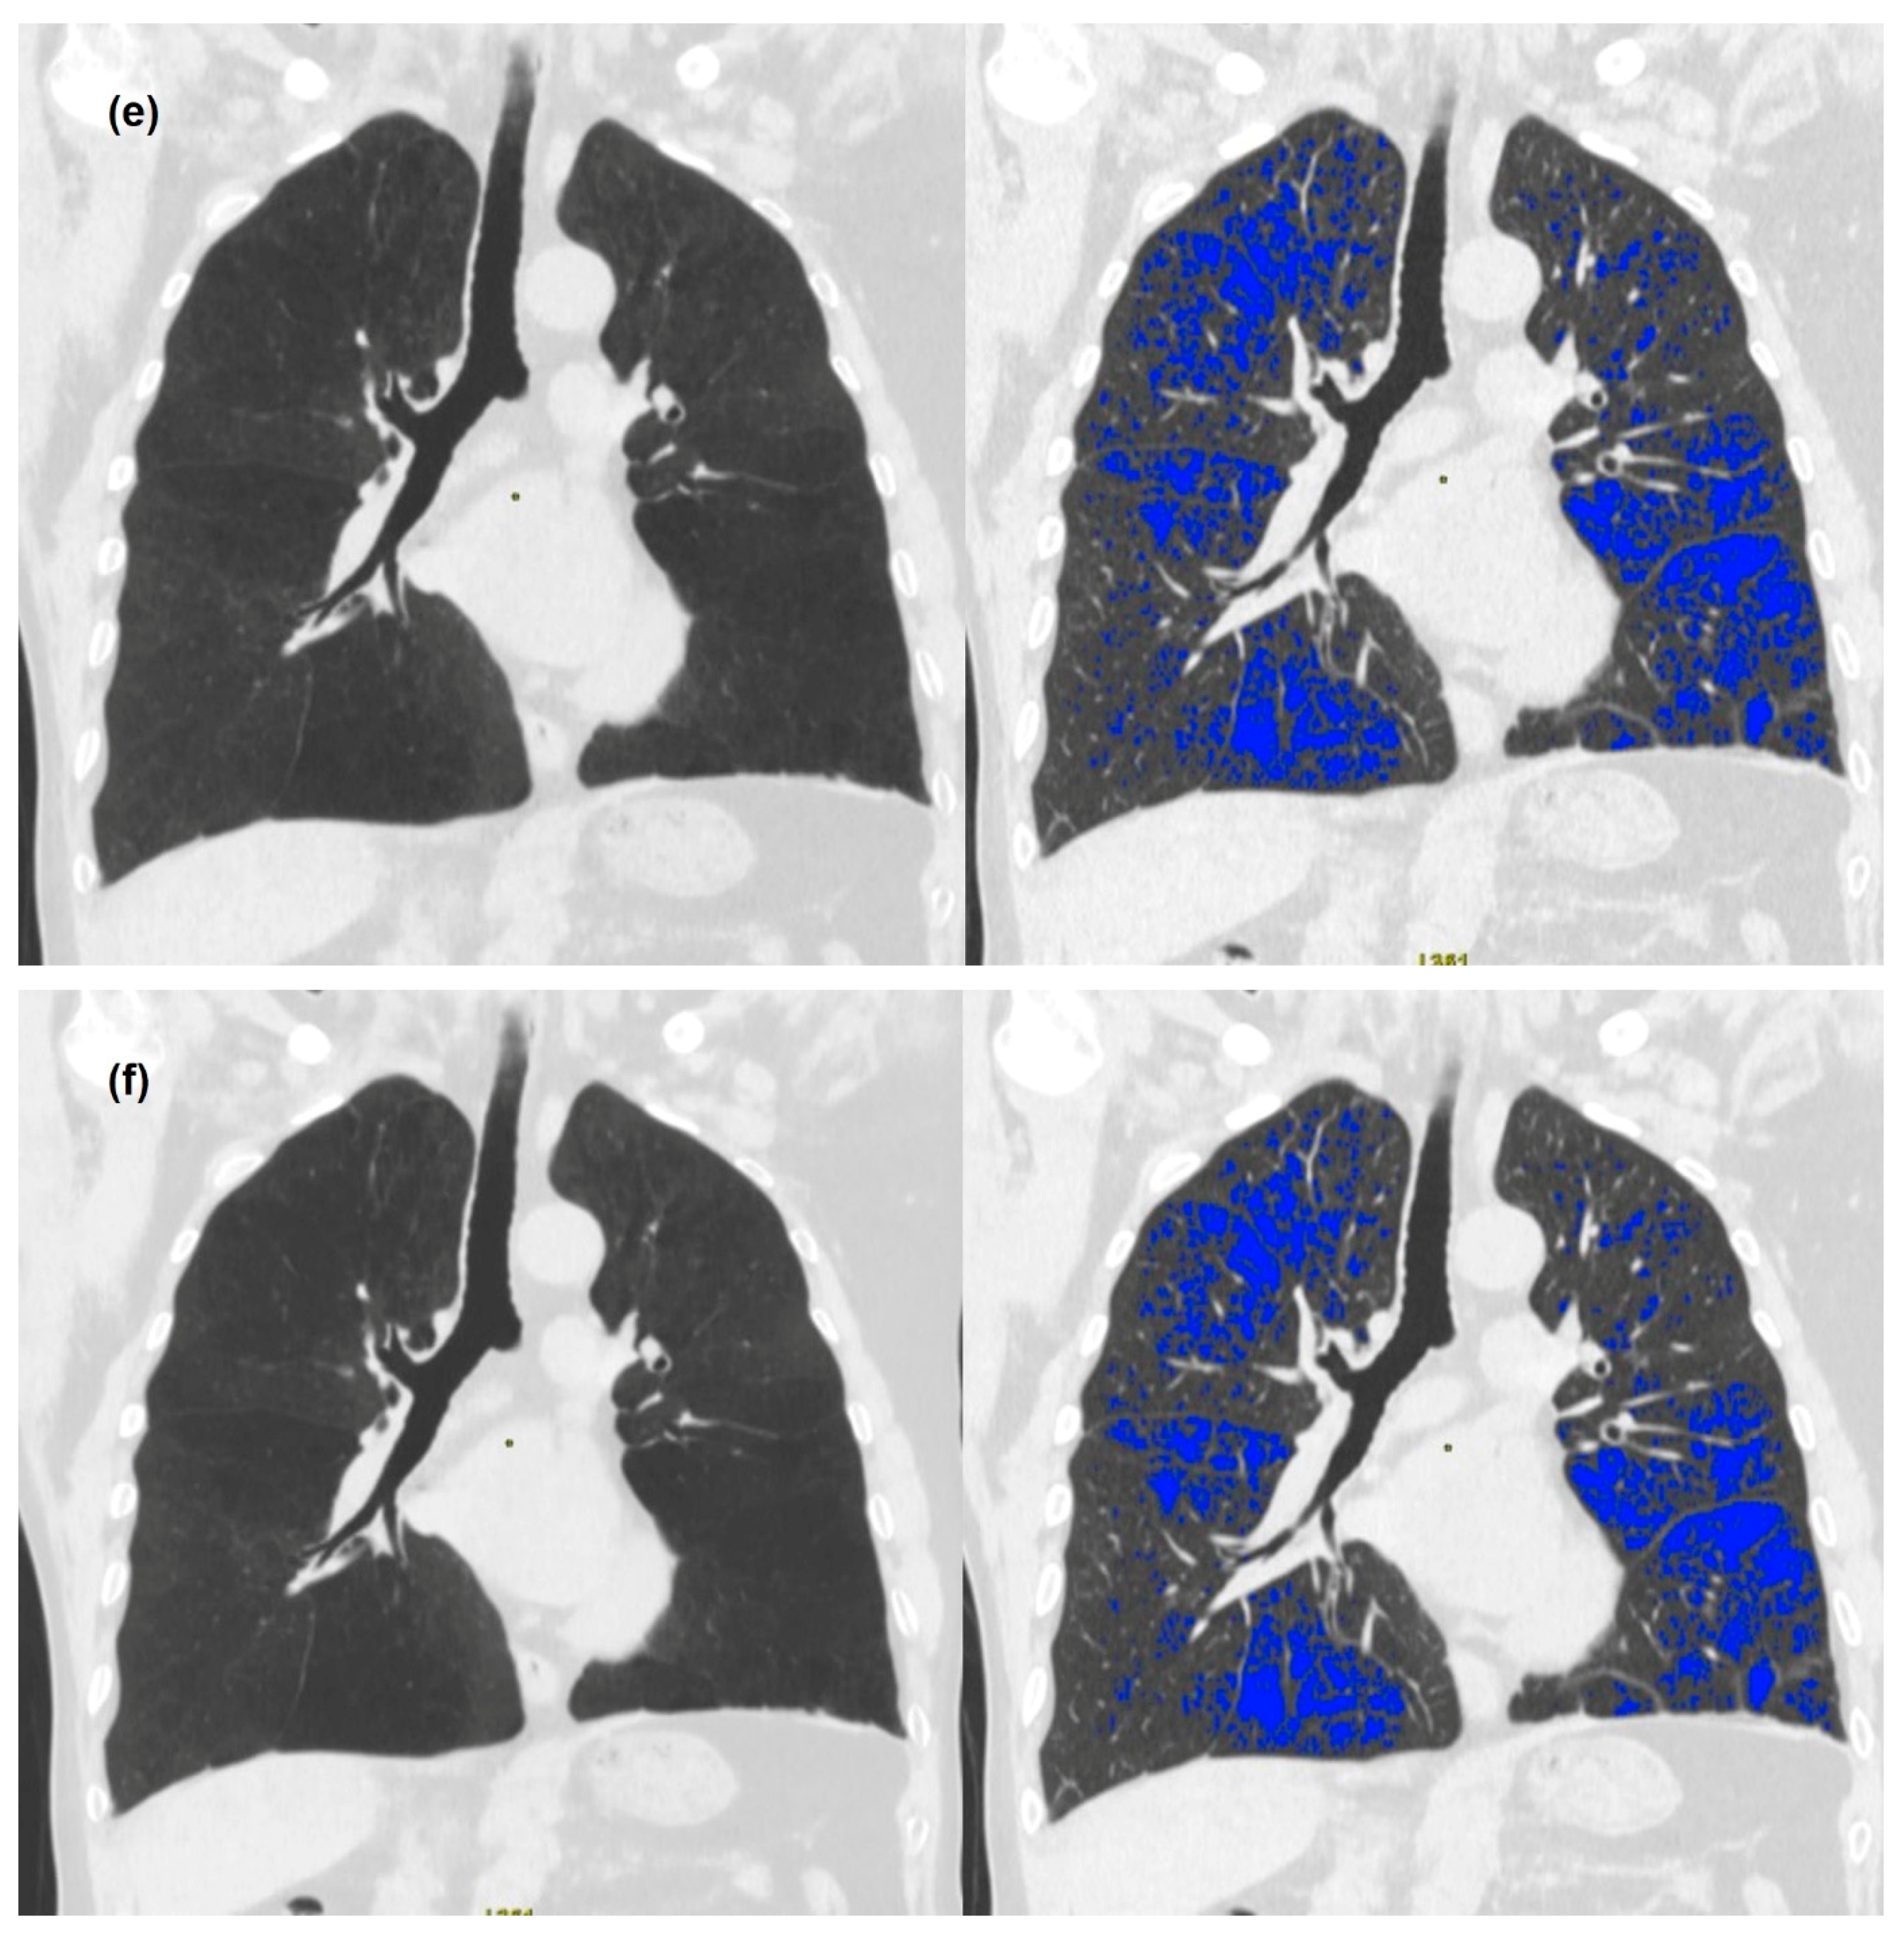

2.3. Image Analysis

3. Results

3.2. Quantitative Measurements of Standard-Dose and Ultra-Low-Dose CT